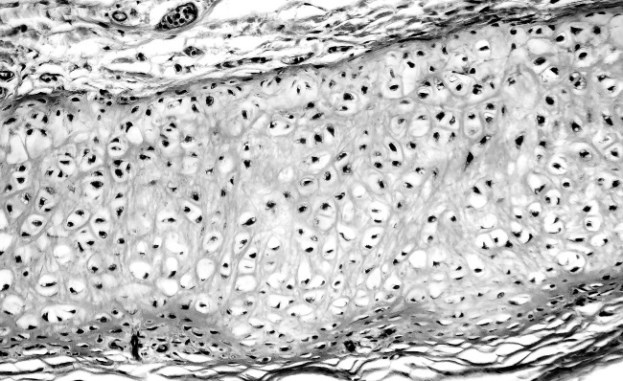

Костные клетки Остеогенные клетки. Эти стволовые клетки – единственные клетки в кости, способные к делению. Они формируют внутреннюю оболочку эндоста (внутренней надкостницы). Остеобласты. Кость – это каркас, или матрикс, создаваемый остеобластами. Остеобласты секретируют вещества, которые становятся основой для коллагеновых белковых волокон. Затем к этим волокнам прилипают, затвердевая, соли фосфата кальция. Остеоциты. За состоянием кости следят более зрелые типы остеобластов – остеоциты. Эти клетки созревают по мере окостенения остеобластов в матриксе. Остеоциты «живут» в небольших участках матрикса, называемых лакунами. Это овальные клетки с множеством отростков. Их цитоплазма проходит по небольшим канальцам, позволяющим остеоцитам взаимодействовать друг с другом и обмениваться полезными веществами или продуктами распада. Остеокласты. Остеокласт не остеогенный по происхождению. Это скорее лейкоцит второго поколения и потомок макрофагов (см. параграф «Белые кровяные тельца» на стр. 146–149). Такие клетки присутствуют в надкостнице и в эндосте. Остеокласты с остеобластами следят за тем, чтобы скорость разрушения и реабсорбции существующей кости не превышала скорость образования новой ткани. В противном случае может возникнуть остеопороз. ![]() У каждого из четырех типов костных клеток своя роль. Губчатая и трубчатая кости В разных костях содержится разное количество костной ткани. Несмотря на то что губчатые и трубчатые кости состоят из одинаковых материалов, их внутреннее строение различается. Трубчатая (компактная) кость Трубчатая кость формирует внешнюю стенку костей. Это второй по твердости материал в нашем организме (после зубной эмали); на его долю приходится 80 % веса костей. Трубчатая кость в разы плотнее губчатой, поэтому такая кость выглядит белой и гладкой. ![]() Трубчатая кость формирует твердую и прочную защитную оболочку вокруг губчатой кости. В ней содержится плотно упакованный костный материал. Трубчатую кость формируют микроскопические столбики (остеоны), которые состоят из концентрических колец остеоцитов. Такое кольцо называют ламеллой (костной пластинкой). В центре каждого остеона располагается Гаверсов канал, выстланный эндостом. В эндосте содержатся нервы, кровь и лимфатические сосуды, которые разветвляются во внешний и внутренний слои кости. Трубчатая кость покрыта надкостницей. ![]() В здоровом состоянии наши кости не ломаются при беге или прыжках, потому что трабекулы губчатой кости смягчают механическую нагрузку. Губчатая (спонгиозная) кость Губчатая кость – это внутренняя костная ткань. Она присутствует на концах длинных костей, костей таза, ребер, позвонков и черепа. Благодаря своей пористой структуре губчатая кость подвижнее и слабее трубчатой кости. Общая поверхность губчатых костей примерно в десять раз больше, чем трубчатых. Губчатая кость состоит из костных балок, или перекладин (трабекул), которые формируют пористую основу. Поверхность трабекулы выстлана эндостом. Характер роста трабекул обусловливается нагрузкой на кость. Пространство внутри трабекул заполнено красным костным мозгом. Остеонов нет, но лакуны заняты остеоцитами (как и в компактной кости). Позвоночные Отличительной особенностью всех позвоночных, будь то ныне живущие или уже вымершие, является наличие внутреннего скелета, или эндоскелета. К позвоночным относятся люди и другие млекопитающие, земноводные, рептилии, птицы и рыбы. Млекопитающие состоят из сотен костей. Например, у синего кита их около 350, а нижний предел у взрослого человека начинается от 206 костей. Считается, что в теле гигантских змей можно насчитать 500 позвонков, и каждый из них прикрепляется к своей паре ребер. Однако у подавляющего большинства змей 120–240 позвонков. Форма костей Как вы уже поняли, кости различаются по местоположению и выполняемым функциям. Внешний вид кости крайне важен, поскольку он определяет выполняемую функцию. Существует пять типов костей. ![]() Мужской и женский скелет Женский скелет миниатюрнее мужского. Но определять пол костного материала на основании морфологических отличий не всегда правильно – из-за естественного разнообразия людей в популяции. Вот несколько интересных гендерных различий. ![]() ![]() Мужские и женские скелеты отличаются по размеру и форме. Хрящ Если кости нужна гибкость, то она идет за помощью к хрящу. Эта гладкая, прочная и подвижная соединительная ткань присутствует во всех суставах у взрослых. Она покрывает концы костей, заменяя надкостницу. ![]() На этом микроснимке изображена структура наружного уха с эластичным хрящом, который расположен между перихондрием. Хрящ, как и кость, образуют клетки, создающие матрикс из хондробластов. Этот матрикс поддерживают более зрелые клетки – хондроциты, обитающие в лакунах матрикса. Под микроскопом хондроциты похожи на игрушечные глазки, которые лежат на ложе из белково-углеводной гиалоплазмы с коллагеном и/или эластином. Будучи аваскулярными, или бессосудистыми, хрящи получают питательные вещества диффузно, через плотную соединительную ткань (перихондрий). Эта мембрана покрывает хрящ, и из-за нее он медленнее заживает после повреждения. Типы хрящей Существует три типа хрящей. Гиалиновый хрящ. Формирует незрелый скелет и сохраняется в виде специальной пластины роста, расположенной в эпифизе длинных костей. Гиалиновый хрящ создает тонкую прослойку на суставных поверхностях костей. Помимо этого, его можно найти в кончике носа и в некоторых участках дыхательных путей: гортани, трахее и кольцах бронхов (см. параграф «Бронхи и бронхиолы» на стр. 171). Гиалиновый хрящ богат разрозненными коллагеновыми волокнами, что делает его гладким и скользким. |